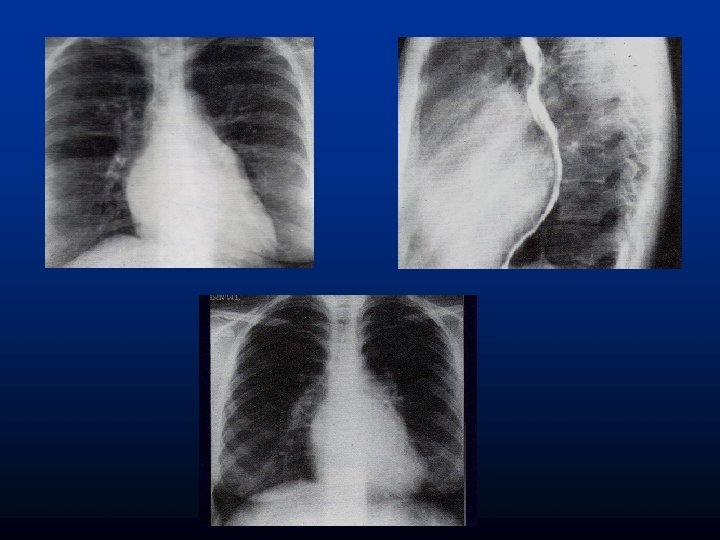

ESTENOSIS MITRAL Rx de torax: Perfil de 4 arcos. HVCP- moteado difuso. Lineas A y B de kerley. Derrame laminar e intercisural. Infiltrado algodonosos= EAP